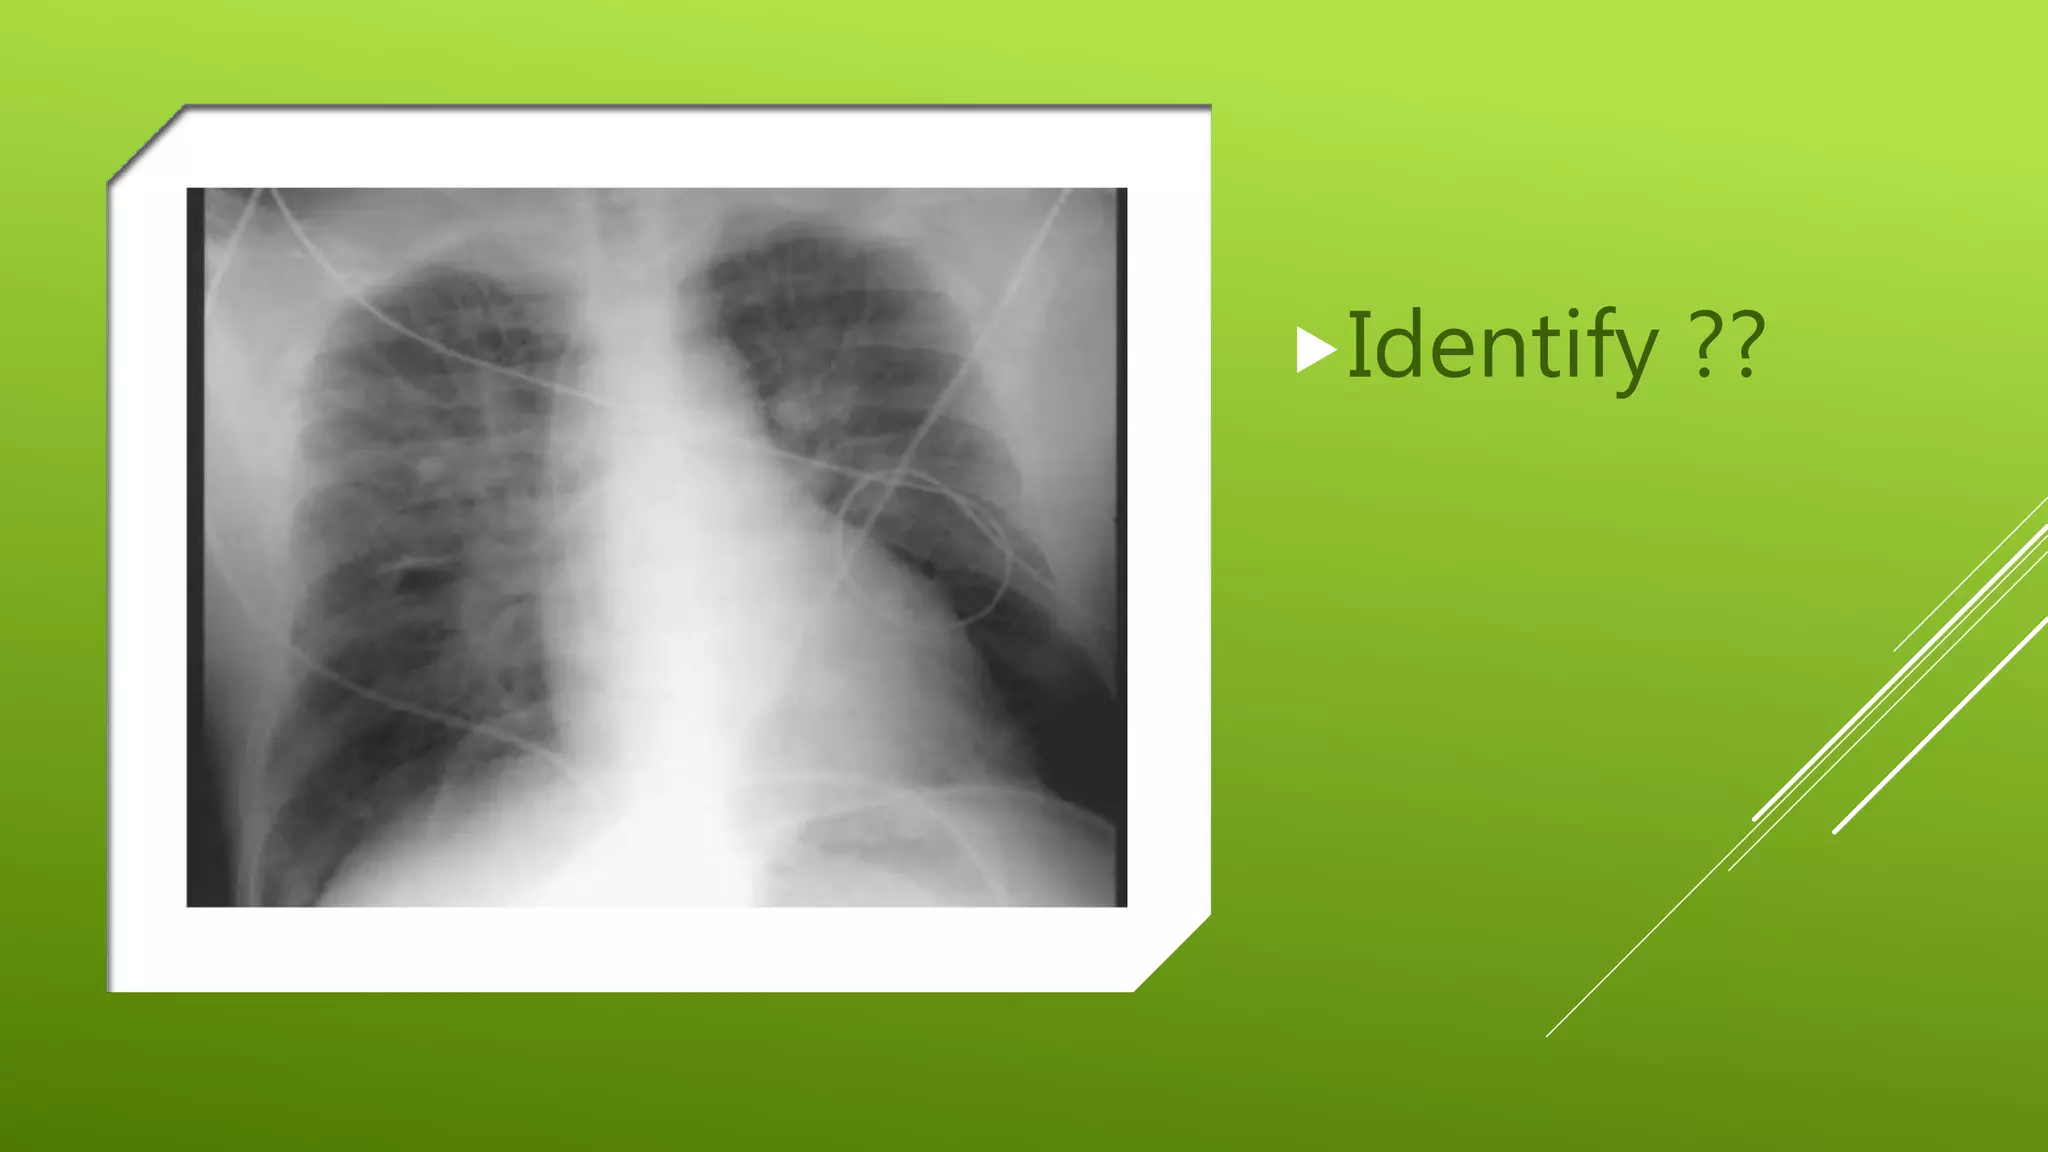

This document contains a series of radiology-related questions and prompts seeking identification and interpretation of various imaging findings, patient presentation details, monitoring values, scoring systems, diagnoses, and management steps. Specific topics include identifying x-ray and CT scan findings, interpreting EKG results, recognizing arrhythmias, assessing intubated and post-surgery patients, and evaluating compliance with treatment plans.